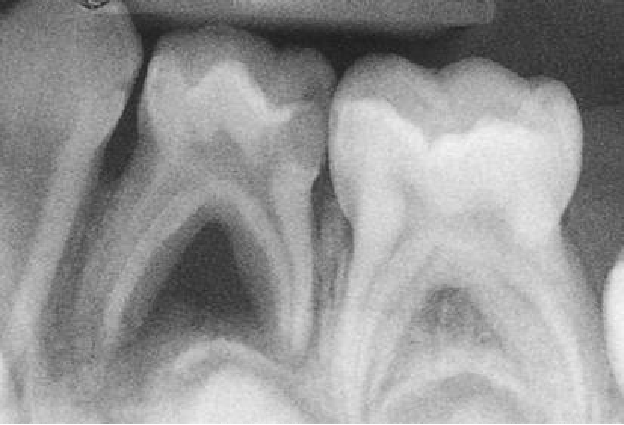

• 上颌乳磨牙大部分有3个牙根,远颊根和腭根常融合;近颊根可能有1~2个根管,远颊根和腭根都只有1个根管。

• 下颌乳磨牙的近中根常见2个根管,远中根常见1个根管,也有2个根管;近中根最常见Vertucci’s types Ⅳ类结构根管,远中根最常见Ⅰ类结构根管;少数存在5个根管。